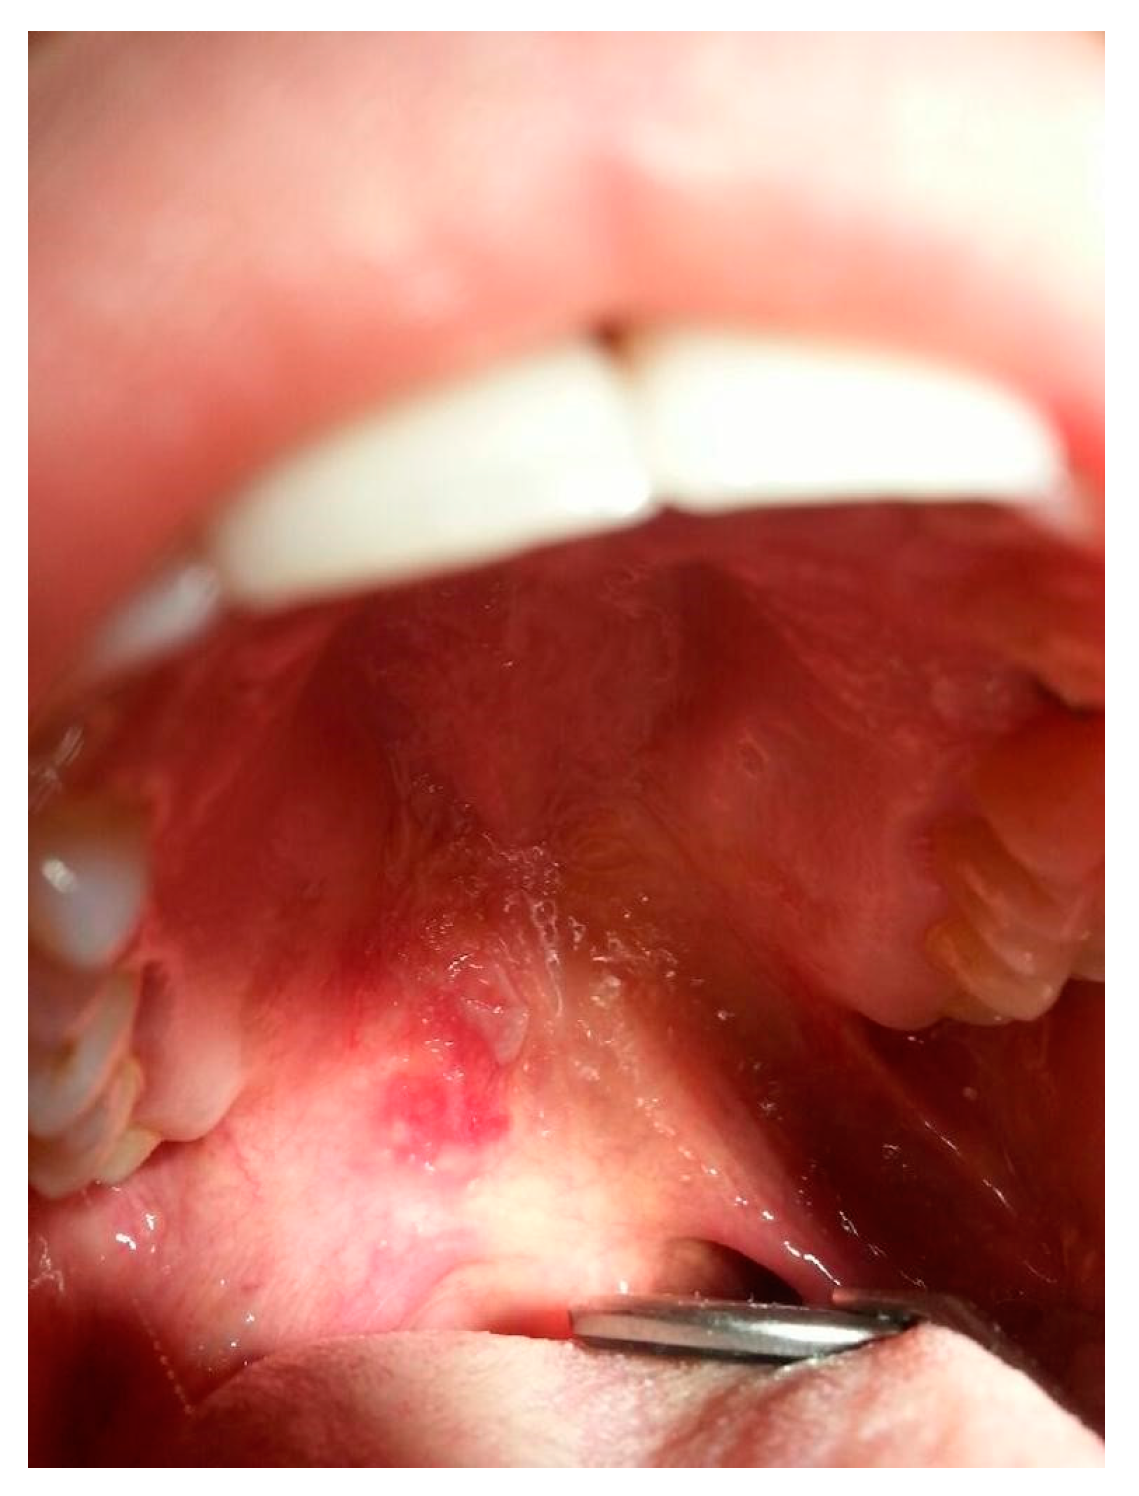

4.10. Mucosal Lupus